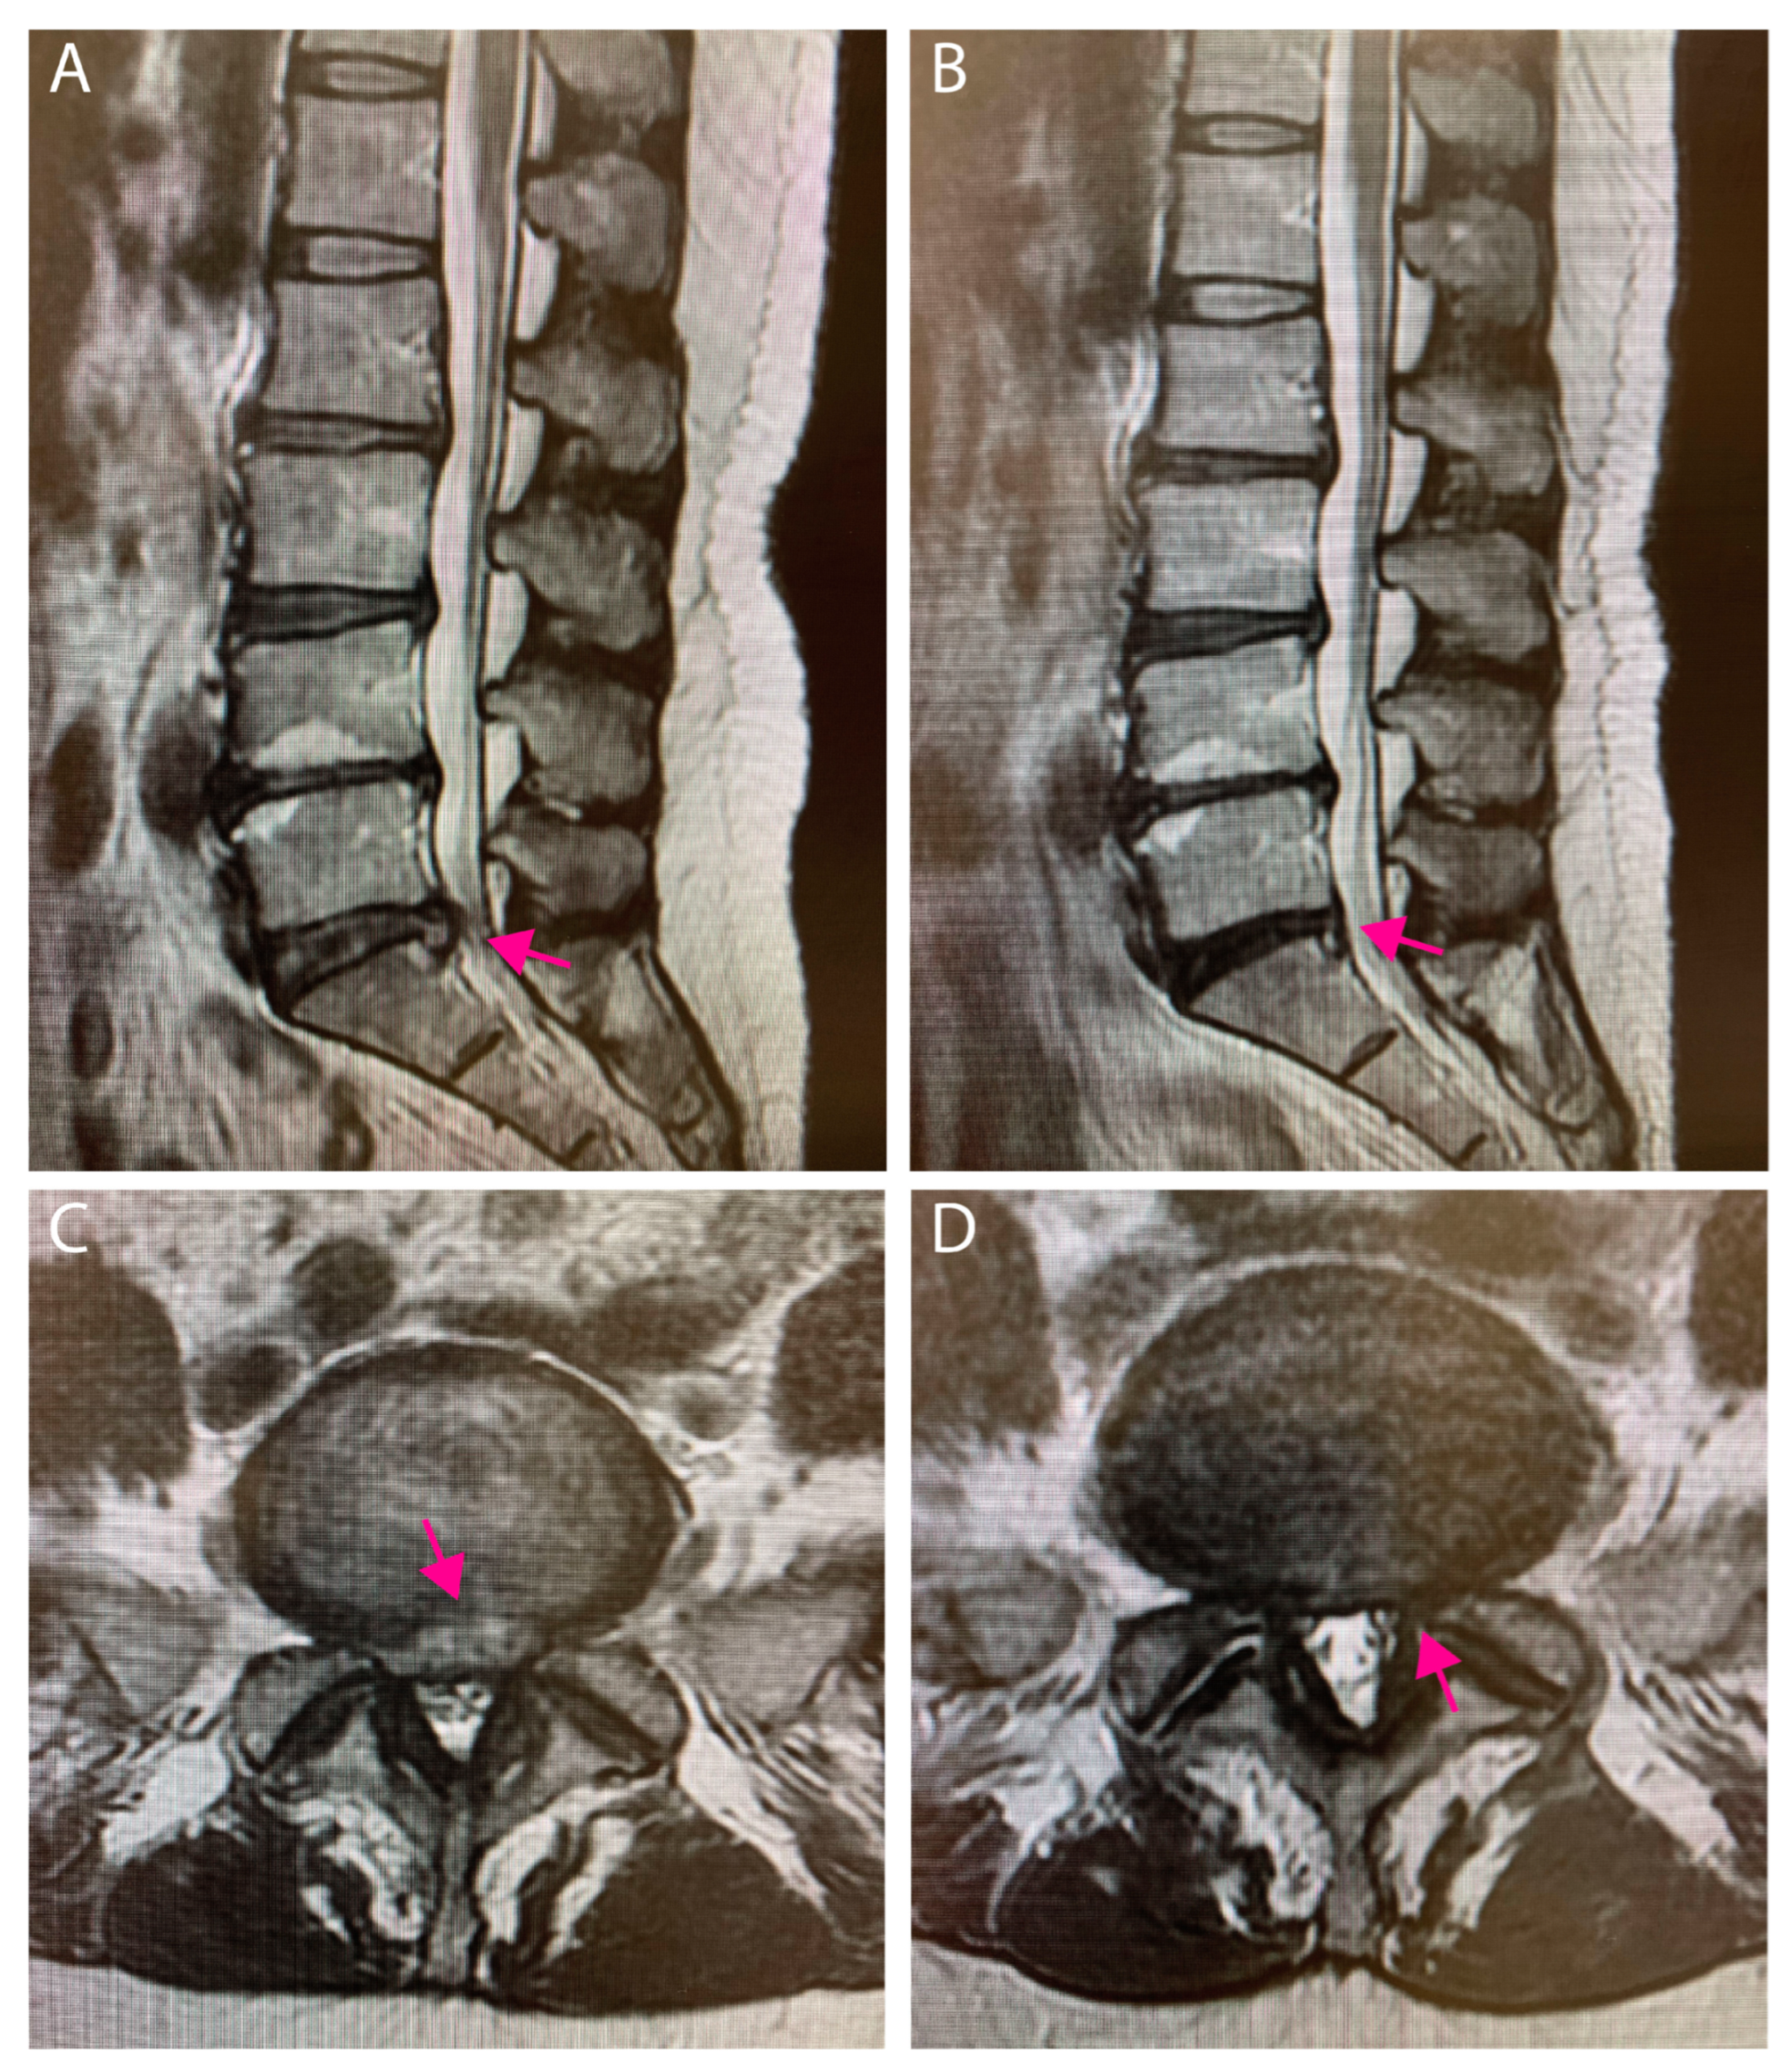

3.3. Case Presentation